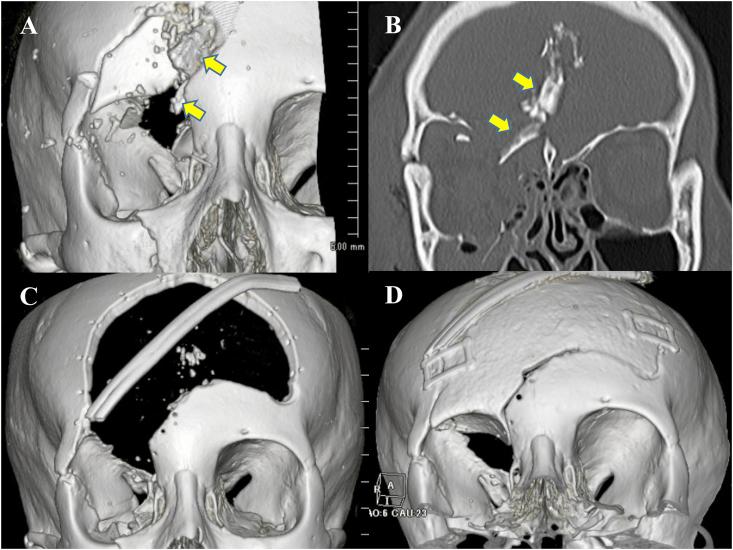

A 23-year-old female was presented with right lagophthalmos. Five months prior to consult at our clinic, she suffered from a penetrating trauma to the frontal lobe of the brain through the right orbital roof with cerebrospinal fluid leakage. Decompressive craniectomy was performed immediately after the injury using a coronal incision, which was followed by reconstruction with an artificial bone 1 month later. On examination at our clinic, she showed right exposure keratopathy with best corrected visual acuity of 20/100 due to corneal opacity. The palpebral contracted scar was first elongated using Z-plasty technique but excursion of the upper eyelid under a finger force assistance was insufficient to eliminate lagophthalmos. However, complete eyelid closure under a finger force assistance was achieved after sharp dissection of the cicatrized adipose tissue from the orbital roof. An autogenous dermis-fat was grafted on the orbital roof and superior orbital rim to avoid adhesion of orbital adipose tissue onto the bone again.

Cicatricial adhesion of an orbital adipose tissue to the orbital roof is one of the possible causes of posttraumatic lagophthalmos in patients with an orbital roof fracture. Surgeons need to be aware of this condition in planning of surgical repair when such a fracture is encountered.